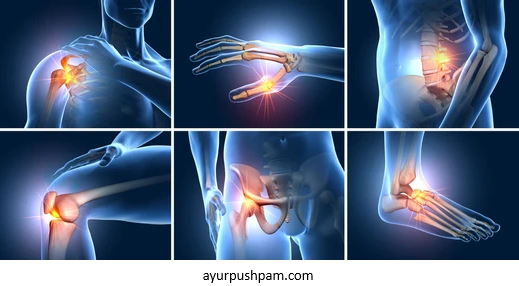

Muscular Pain

Ayurveda provides various natural treatments for muscular pain, aiming to alleviate discomfort and promote the body's natural healing process. Ayurvedic treatments typically involve a combination of external therapies, internal herbal remedies, and lifestyle adjustments.

Chronic Joint Disorders

Ayurveda offers a comprehensive approach to treating chronic joint disorders, focusing on reducing pain, inflammation, and restoring joint function. Ayurvedic treatments for chronic joint disorders aim to address the underlying imbalances, promote joint health, and enhance overall well-being.